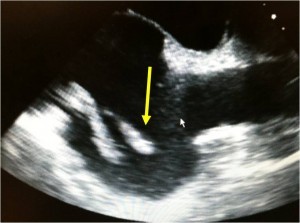

- “Clot-in-transit”- Echocardiography or cross-sectional imaging (CT angiogram) may demonstrate thrombus that is within the inferior vena cava or right heart chambers, often threatening to dislodge and enter the pulmonary circulation.